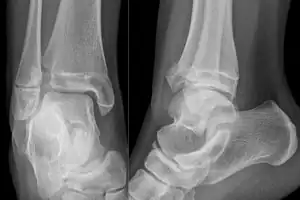

| X-ray of a Tillaux fracture in an 11 year old female | |

A Tillaux fracture is a Salter–Harris type III fracture through the anterolateral aspect of the distal tibial epiphysis.[1] It occurs in older adolescents between the ages of 12 and 15 when the medial epiphysis had closed but before the lateral side has done so,[2] due to an avulsion of the anterior inferior tibiofibular ligament, at the opposite end to a Wagstaffe-Le Fort avulsion fracture

The presentation of Tillaux fracture is pain and swelling in anterior lateral part of ankle[3]

The fracture commonly results from an abduction-external rotation force, causing the anterior tibiofibular ligament to avulse the anterolateral corner of the distal tibial epiphysis resulting in a Salter Harris Type III fracture.